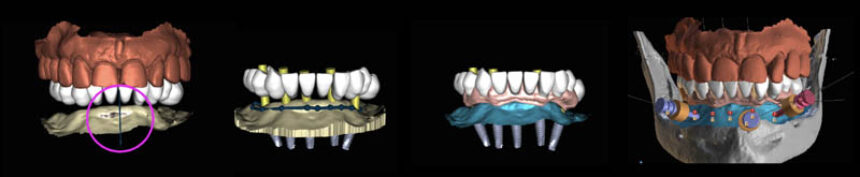

The modern day clinician is constantly receiving information regarding digital dentistry and computer-guided implantology. Inevitably it leads to information overload leaving the dentist overwhelmed about the whys and hows and whether these new technologies can really help him in his daily clinical practice. Together we will discuss and analyze the details and steps behind each digital tool and how we will start incorporating them correctly into our clinic, always using them guided by the biological factors that rule implantology.

"Guided implantology and digital dentistry.

Just another trend or tools to

enchance biology and healing? "

Dimitris Chatziemmanouil

Hands-on Practice :

"A to Z.

Scan, Plan and execute fully guided anterior immediate implant and provisionalization with the use of Cervico”